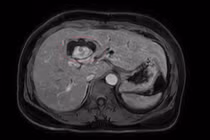

benh-wilson2.jpg

Các triệu chứng của người bệnh được cải thiện rõ rệt sau 2 năm điều trị - Ảnh BVCC